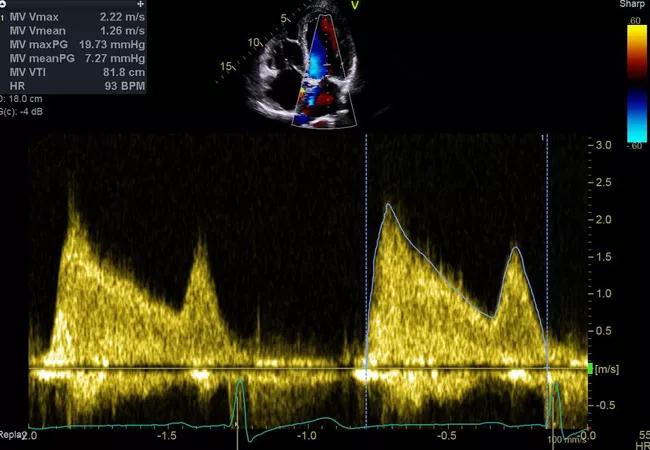

Echocardiograms from a patient with mitral stenosis before (top) and after (bottom) surgical intervention.